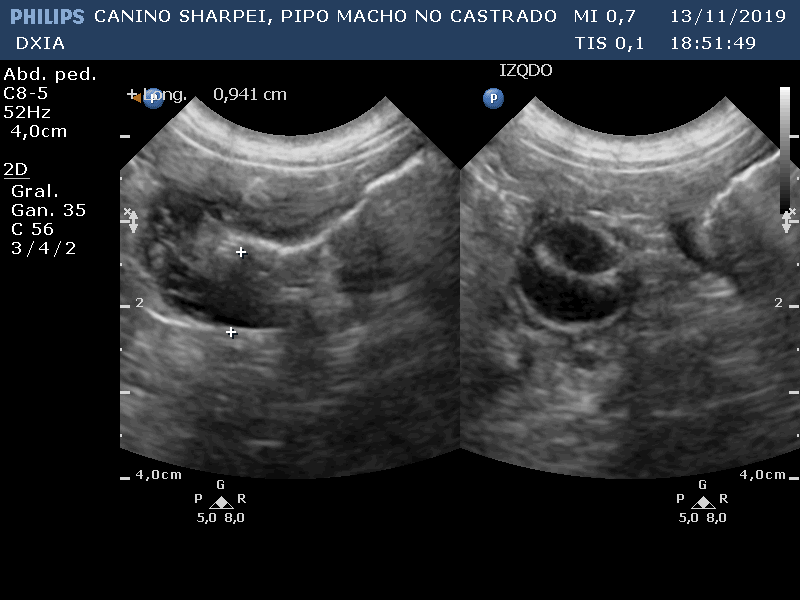

PIPO

Del informe ecográfico de Pipo se destaca la existencia de varias alteraciones:

Comentario imágenes A y B: Comparativa Asas ID normal con asa alterada donde se observa aumento de la pared (engrosamiento) con pérdida de estructura en capas.

Neoformación en ID de la que se realiza PAF ecoguiada.